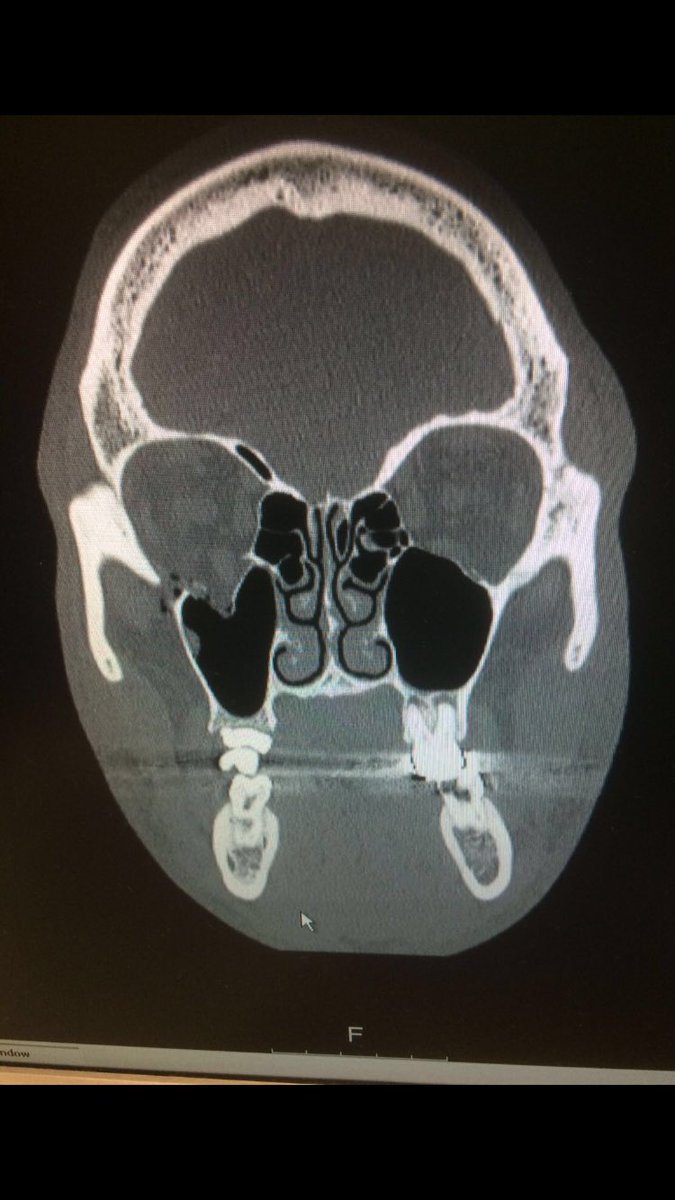

Promoter Eddie Hearn has confirmed that Kell Brook suffered a Broken eye socket during his fifth round defeat against Gennady Golovkin on Saturday night.

Hearn tweeted the x-ray pic below